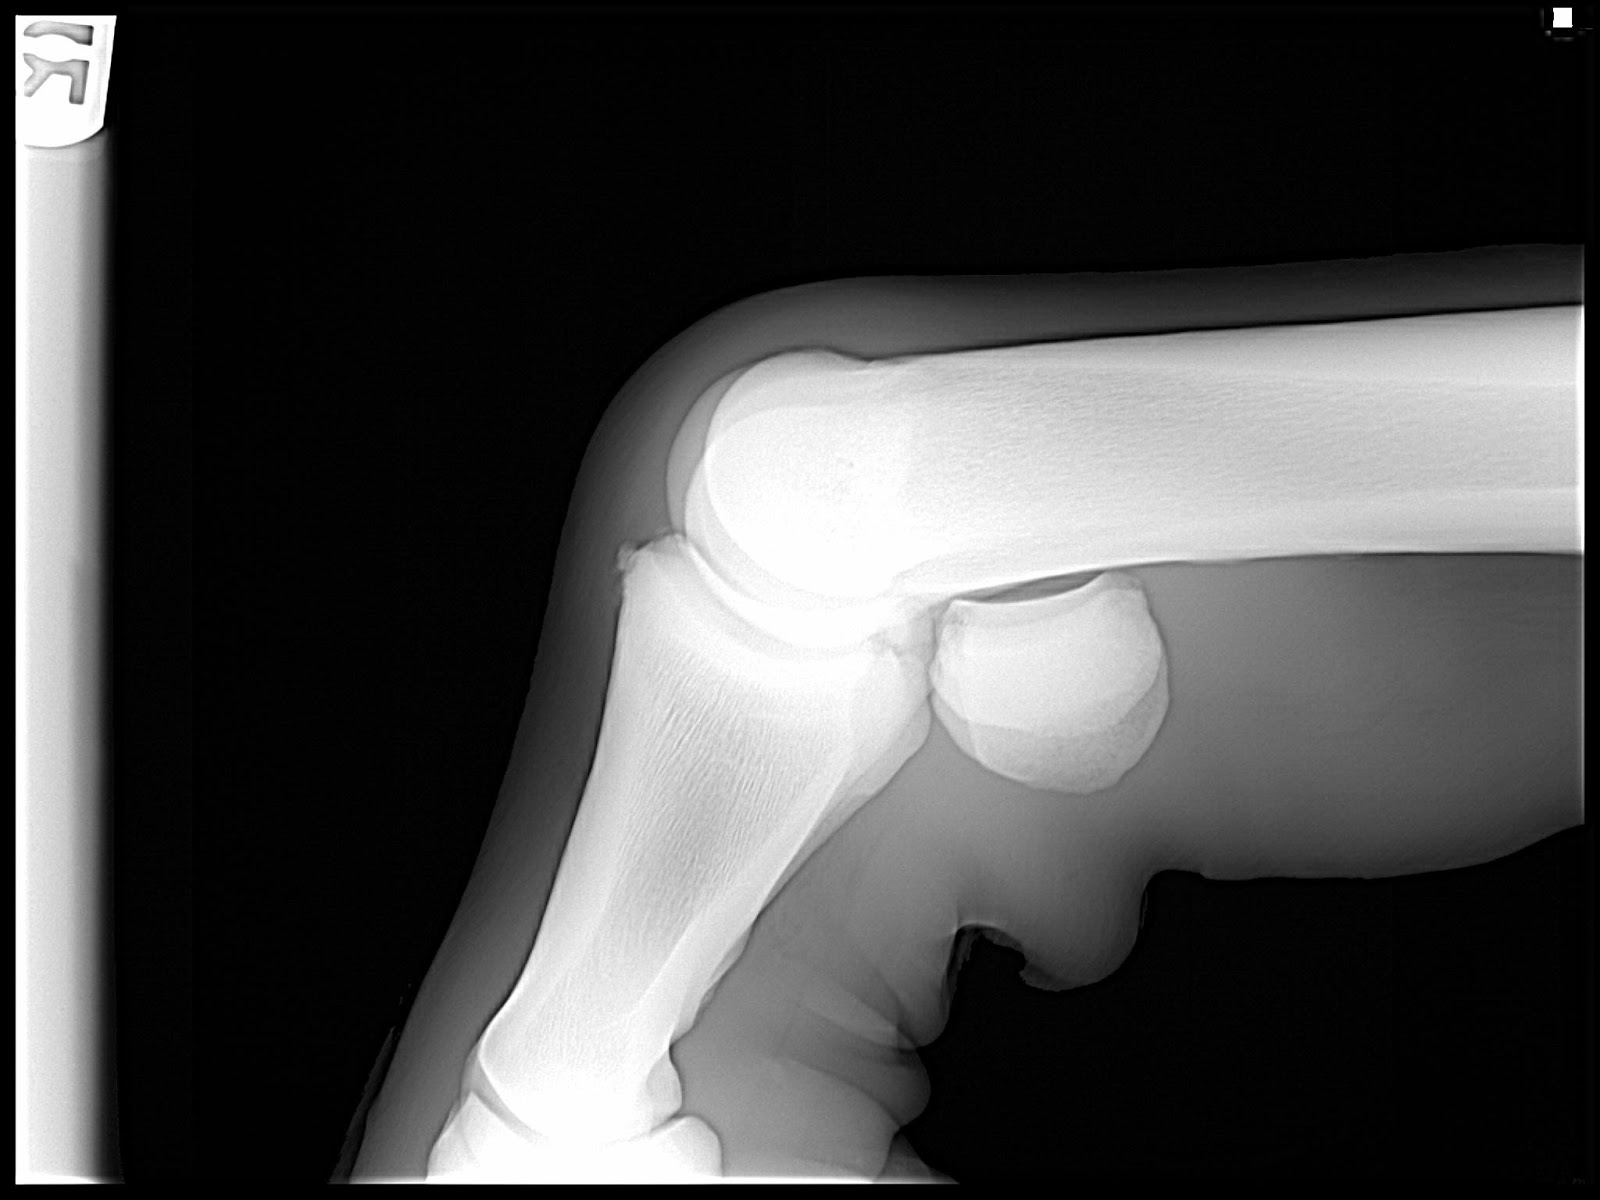

It was a very stormy day but the vet and I managed to complete a lameness exam and take X-rays of the right hind leg, as well as a couple of extras of the other legs just to make sure everything was ok with them. The vet studied the X-rays and saw what he said was something very interesting going on with the right hind fetlock.

Something I had never dreamed of; bone chips! My heart sank as I knew this was not going to be easy. The vet said that Lexi had a lot of fluid not only in the fetlock, but in both upper hocks as well, probably as a result of shifting her weight onto the left leg for relief. He suggested some joint injections to relieve the inflammation, and said that he would refer us to a surgeon for a consultation on the bone chips.

Went to my vet/surgeon consult December 11 and the surgeon was great. He spent over an hour with me looking at all the X-rays and pictures of the swelling. Not only did he see the main chip, he also saw some chip flakes above the main one that I didn't see. He said that the location of the chips and the hard swelling weren't "textbook", and that he wanted to see Lexi in person before committing to surgery on her. I agreed, and made another appointment to bring her in.

Bone chips or chip fractures of horse's joints are properly termed "osteochondral fragments". Osteo (Latin for bone) and chondral (Latin for cartilage) describe the make-up of the fragments that can cause irritation and lameness in a horse's joint. In horses, the major component of the fragment is normally bone. Fragments (chips) occur for two main reasons:

The chip fractures that cause problems are those that cause debris to be shed within a joint and irritate the joint. Debris causes acute painful inflammation. If the debris shedding stops, the joint can heal. If the the debris shedding is chronic, then arthritis results. The size of chip can range from small to large, but the size does not matter. It is the amount of debris that is shed that matters.

Lexi's chip fractures are definitely shedding debris, hence the excess fluid and swelling. I know in my heart that there is no other option but surgery for her to have a normal and productive life.